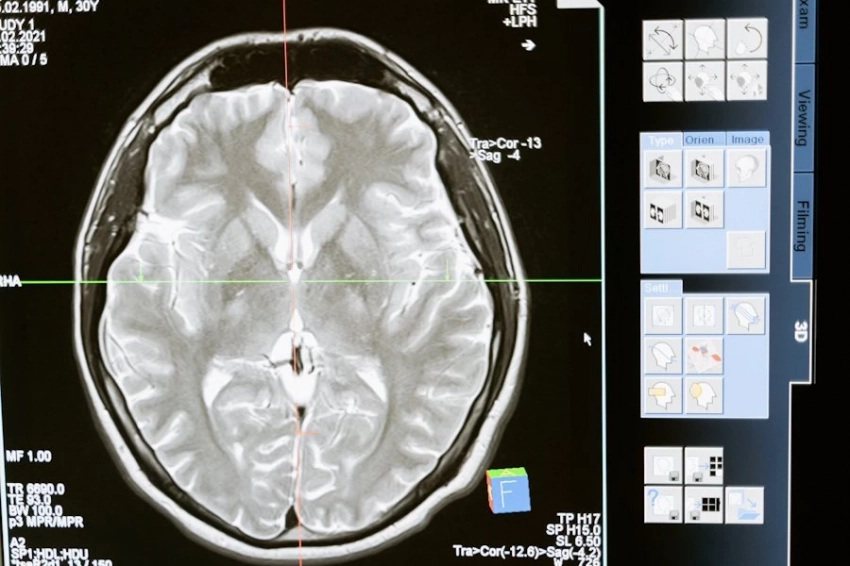

Фото из открытых источников Специалисты НГУ разработали инновационный программный модуль, способный проводить дифференциальную диагностику опухолей мозга по МРТ-снимкам. Как сообщает пресс-служба Новосибирского государственного университета, система демонстрирует значительную эффективность в обнаружении и анализе...